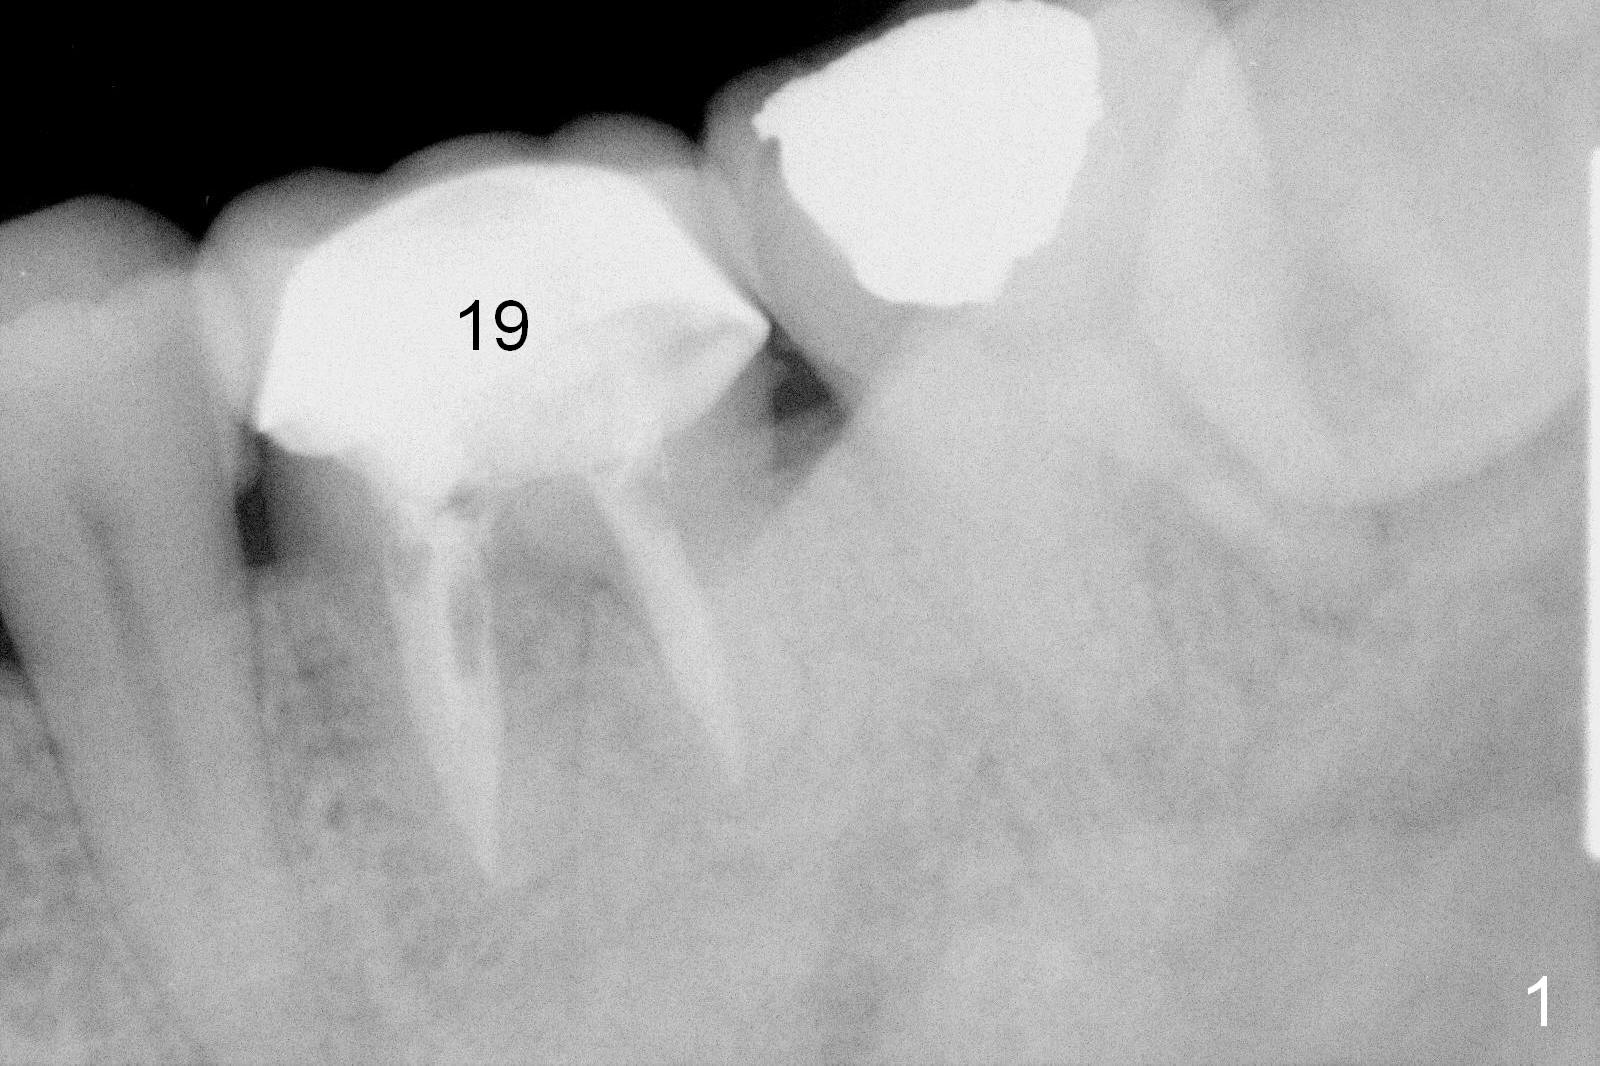

The tooth #19 of a 54-year-old man (FJ) looked normal 2.5 years ago (Fig.1). The patient returns because of 3 fistulae developing around the mesial root of the tooth. Recent PA shows a large radiaolucent defect (Fig.2,3). To place an implant in the middle of the edentulous space, initial osteotomy should be distal because of the large mesial defect.